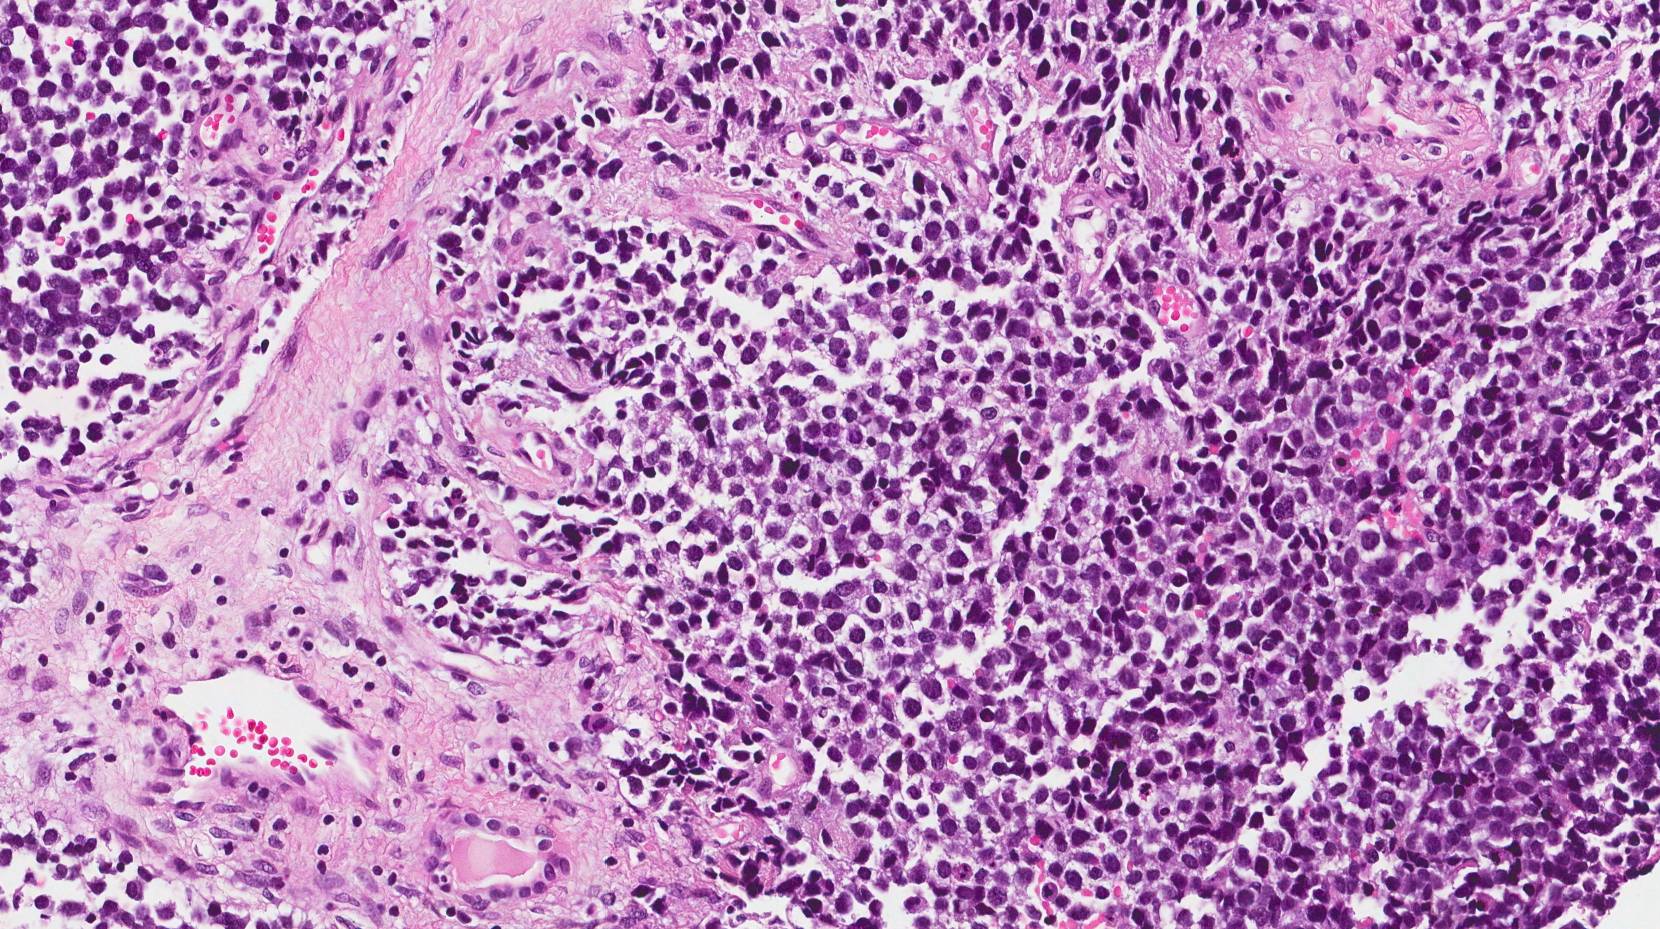

Soft Tissues: Alveolar Rhabdomyosarcoma

Alveolar Rhabdomyosarcoma, Magnification 20. Dyshesive And Infiltrative

rhabdomyosarcoma alveolar infiltrative magnification

(A) Histological Appearance Of Alveolar Rhabdomyosarcoma: Fibrous

alveolar rhabdomyosarcoma fibrous histological connective septa forming

(A) Histological Appearance Of Alveolar Rhabdomyosarcoma: Fibrous

alveolar rhabdomyosarcoma histological fibrous septa connective figure forming findings implications prognostic pseudo

Alveolar Rhabdomyosarcoma; A. Typical Architecture With Pseudoalveolar